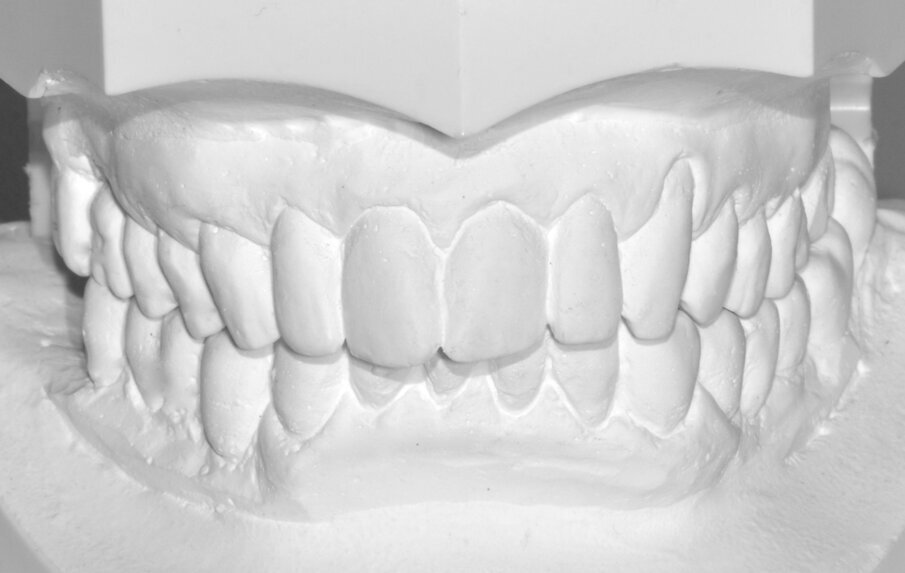

Da un punto di vista protesico verranno eseguite corone singole in zirconia stratificata sugli elementi 13-12-11-21-22 e una faccetta in disilicato di litio sul 23. A causa della notevole rotazione dei due incisivi centrali in fase di ceratura abbiamo optato per due corone complete anziché due faccette per una migliore distribuzione degli spazi protesici dei quattro incisivi (Fig. 8). Il gruppo frontale inferiore invece verrà protesizzato con corone in zirconia stratificata sugli elementi 32-31-41-42-43 splintate per compensare una mobilità di grado 1 dei quattro incisivi.

Inizialmente vengono applicati i provvisori prelimatura (Fig. 9) utilizzati anche come mock-up per passare dopo le opportune valutazioni estetiche (Figg. 10, 11) a una seconda serie di provvisori che ci accompagnaranno durante la fase chirurgica e il tempo di guarigione e maturazione dei tessuti. Prima si procede con la chirurgia resettiva (ORS) sul canino superiore destro per alzare la parabola gengivale a livello degli altri denti frontali; questo intervento viene eseguito con un approccio “delicato” e meno invasivo possibile per non penalizzare l’estetica della corona preesistente sul primo premolare superiore destro.